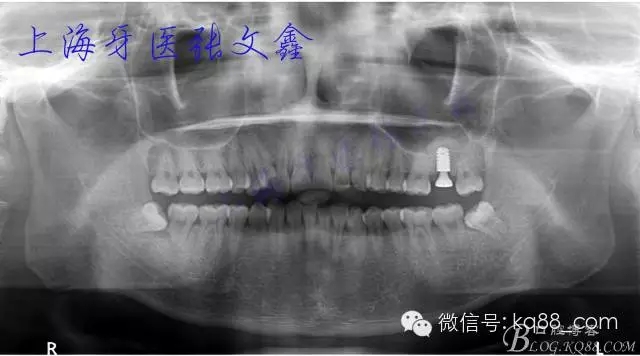

填入骨粉,植入種植體(ankylos B4.5)

術(shù)后全景片